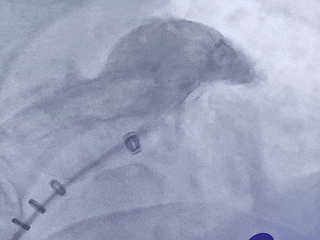

术中DSA左心耳造影

肝位左心耳造影

右肩位左心耳造影

-

心耳呈反鸡翅,穿刺位置偏下偏前